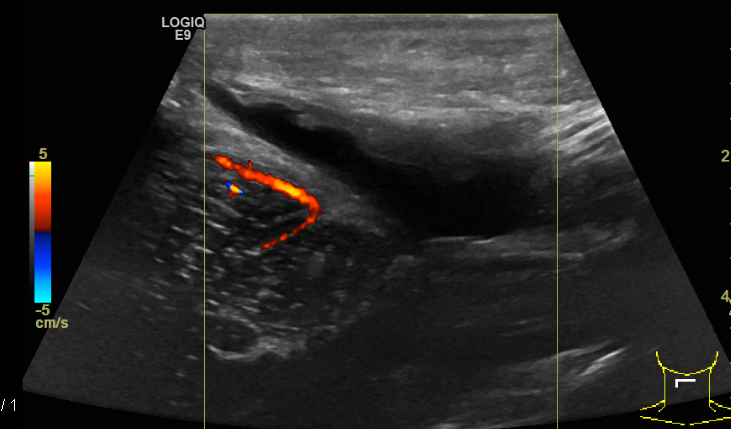

El 23 de enero del 2020 tuve mi segunda revisión de control en el hospital con un ultrasonido. El doctor tuvo los resultados primero y cuando entré a su consultorio estaba muy sonriente y sorprendido de mi recuperación. Yo conocía esa sonrisa. A finales de noviembre el quiste medía 6.8 x 3.5 x 1.6 cm y 20 centímetros cúbicos, y en enero 5.5 x 2.4 x 1 cm y 7.6 centímetros cúbicos.

"Aunque su tamaño no se redujo mucho, sí lo hizo en volumen de centímetros cúbicos: se redujo a más de la mitad de su volumen, lo que quiere decir que seguramente la fístula ya cerró. Ahora es cuestión de esperar a que el cuerpo de manera natural termine de reabsorber el resto del agua como lo ha venido haciendo y, para estar completamente seguros, podrías hacerte otro control a finales de marzo". Esta vez consciente y desde el fondo de mi corazón me sentí muy pero muy feliz: al fin se estaba poniendo fin a esta pesadilla, no más cirugías, no más hospitales, solo cuidados y tiempo. ¡Gracias, gracias, gracias Dios!